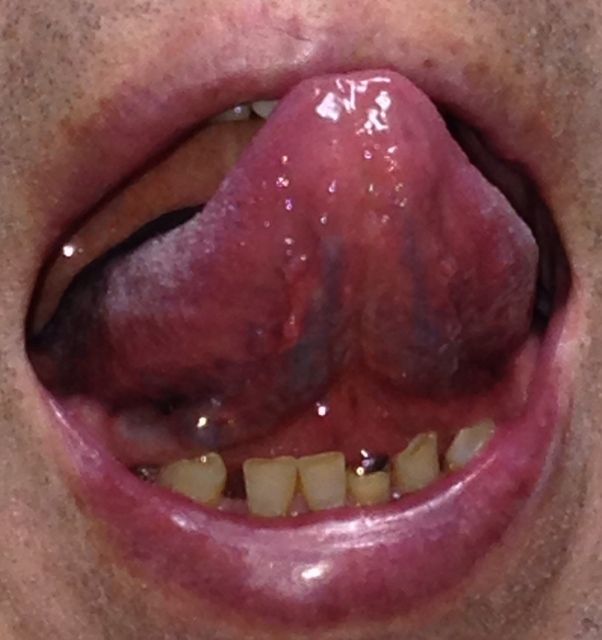

¡Ú2013ǯ7·î17Æü¡¦´ÁÊýÌôÉþÍÑ35Æü¸å¤ÎÀå¤Îɽ¡Û

¡Ú2013ǯ10·î14Æü¡¦´ÁÊýÌôÉþÍÑ92Æü¸å¤ÎÀå¤Îɽ¡Û

¡Ú2013ǯ6·î14Æü¡¦´ÁÊýÌôÉþÍÑÁ°¤ÎÀå¤Î΢¡Û

¡Ú2013ǯ7·î17Æü¡¦´ÁÊýÌôÉþÍÑ35Æü¸å¤ÎÀå¤Î΢¡Û

¡Ú2013ǯ10·î14Æü¡¦´ÁÊýÌôÉþÍÑ92Æü¸å¤ÎÀå¤Î΢¡Û